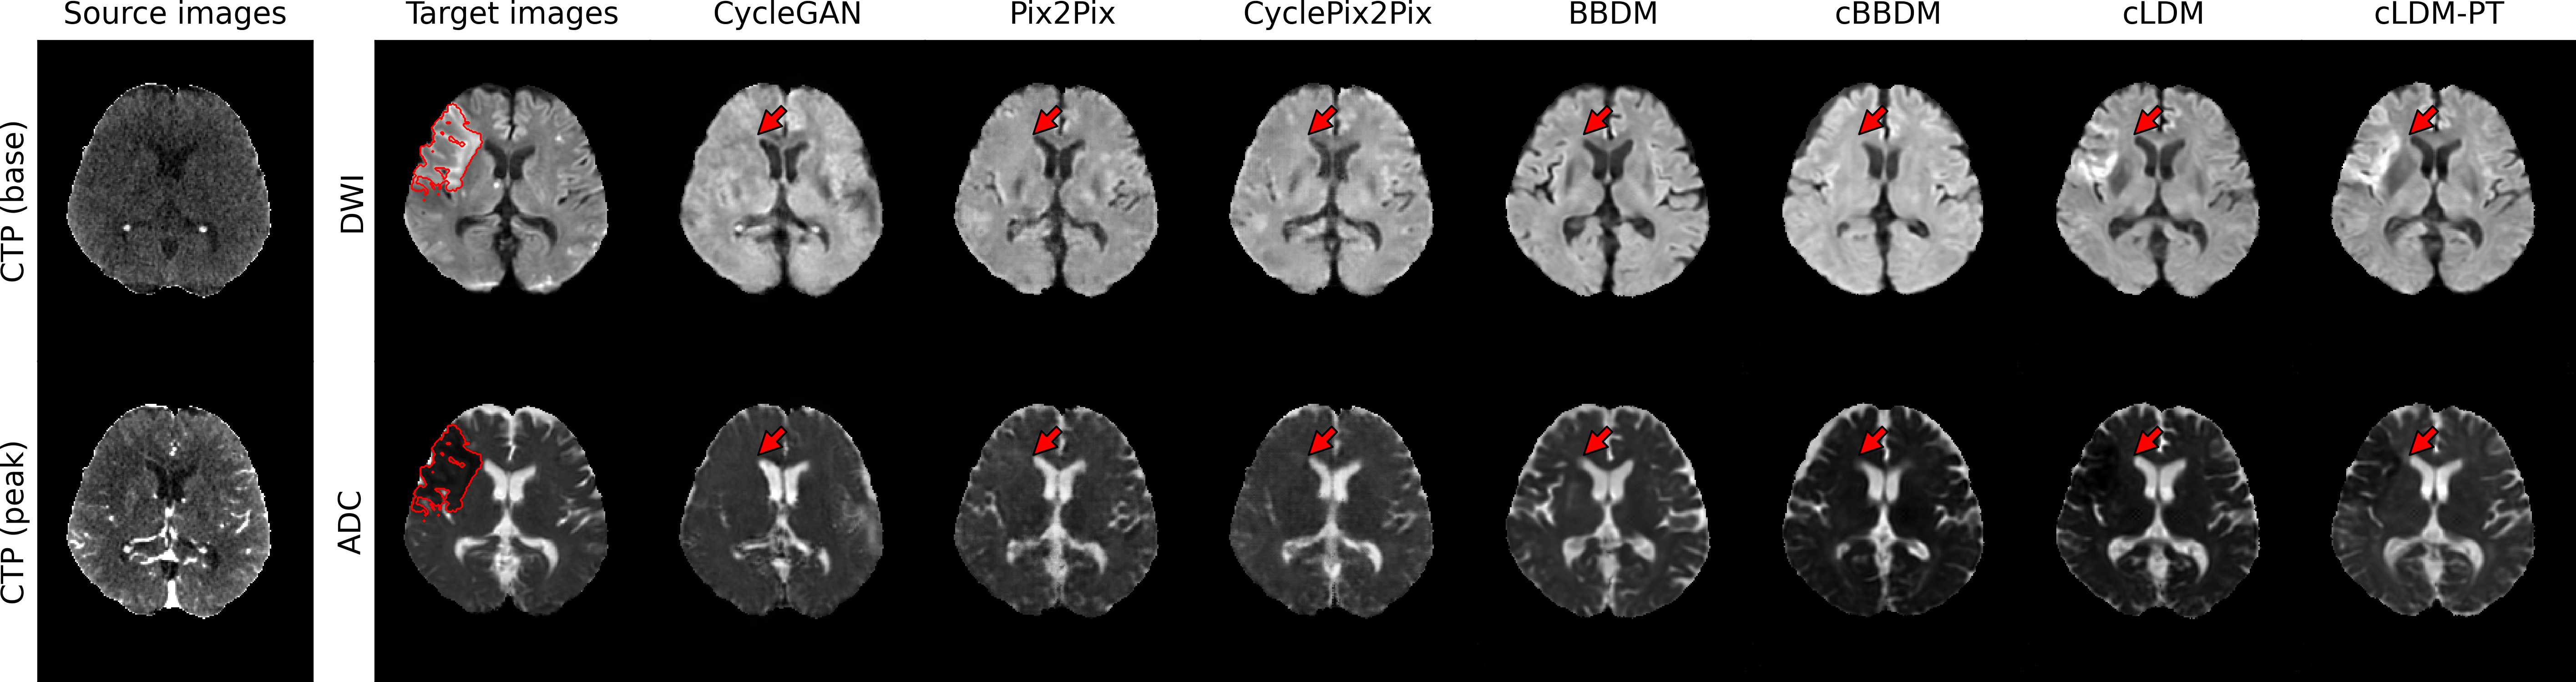

3.2.2 Qualitative Evaluation

Figure 3 visualizes synthesized DWI and ADC from CTP of acute ischemic stroke patients with lesions in various brain regions. Due to low signal-to-noise ratio of CTP, it is difficult to accurately estimate ischemic core volumes. Small infarcts such as lacunar infarcts are also poorly visualized in CTP. These factors make it challenging for generative models to accurately reconstruct ischemic lesions in synthesized MRI. While the diffusion model series generates more realistic images compared to GAN-based models, they encounter difficulty in lesion delineation. Our model, cLDM-PT, excels in lesion delineation and demonstrates exceptional ability to generate accurate and detailed images.